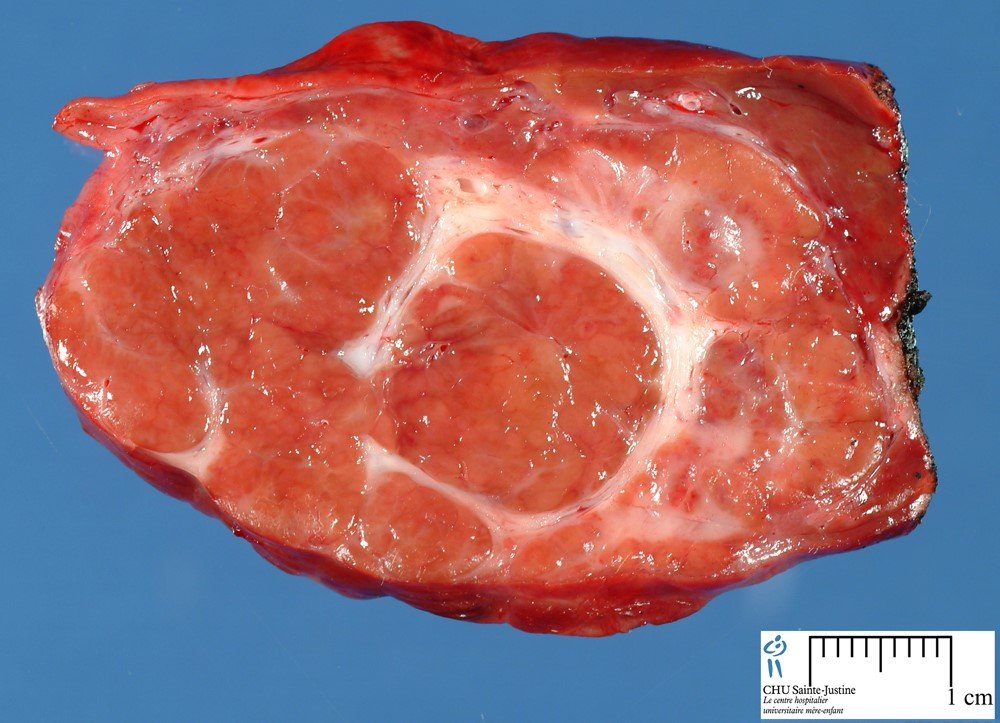

• Histoloji cəhətdən embrional hepatositlərə bənzəyən hüceyrələrdən təşkil olunmuşdur.

• Şiş daxilində osteoid, qığırdaq, fibroz tipli mezenximal toxumalara da rast gəlmək olur.

• Osteoid toxumanın və nekrozun olması ilə əlaqədar şiş daxilində kalsifikasionlar tez-tez (30%) müşahidə olunur.

• Ən çox sağ payda yerləşir, ölçüləri 1-2 sm-dən 10-15 sm-ə qədər dəyişə bilir.

• Qaraciyər parenximası əksər hallarda normal olur.

Şəkil. Hepatoblastoma